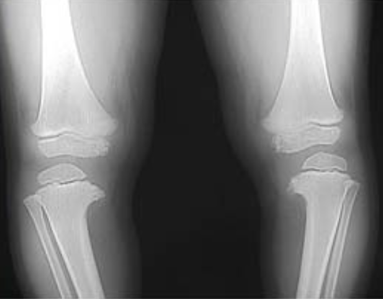

Maladie de Blount

défaut de croissance du tibia interne supérieur: bilatérale 60%

- Lesion métaphysaire tibiale interne

-Angle entre physe et la diaphyse

Déformation en varus: jambes arquées de longueur différente

proéminence médiane du tibia proximal